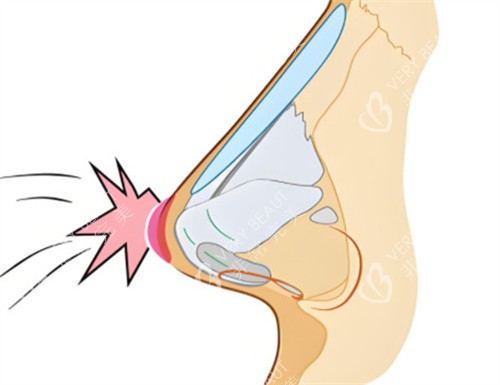

李保锴医生重视鼻部整体力学结构的重建。他提出结构一体化修复概念,强调支撑与自然的统一。这种方式避免传统分段修复的不足,增强鼻部抗外力能力。

他采用肋软骨微雕重塑鼻部支撑,减少再次变形的风险。创新的取肋技术切口小且位置隐蔽,改善后痕迹不明显。动态平衡技术使鼻部触感柔软,仿生结果良好。

对于多次修复失败的鼻子,如挛缩或穿孔情况,他使用复合材料进行重建。结合自体真皮移植和鼻基稳定术,改善功能并延长形态维持时间。